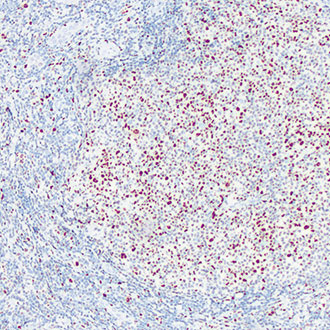

CD8

CD8 -